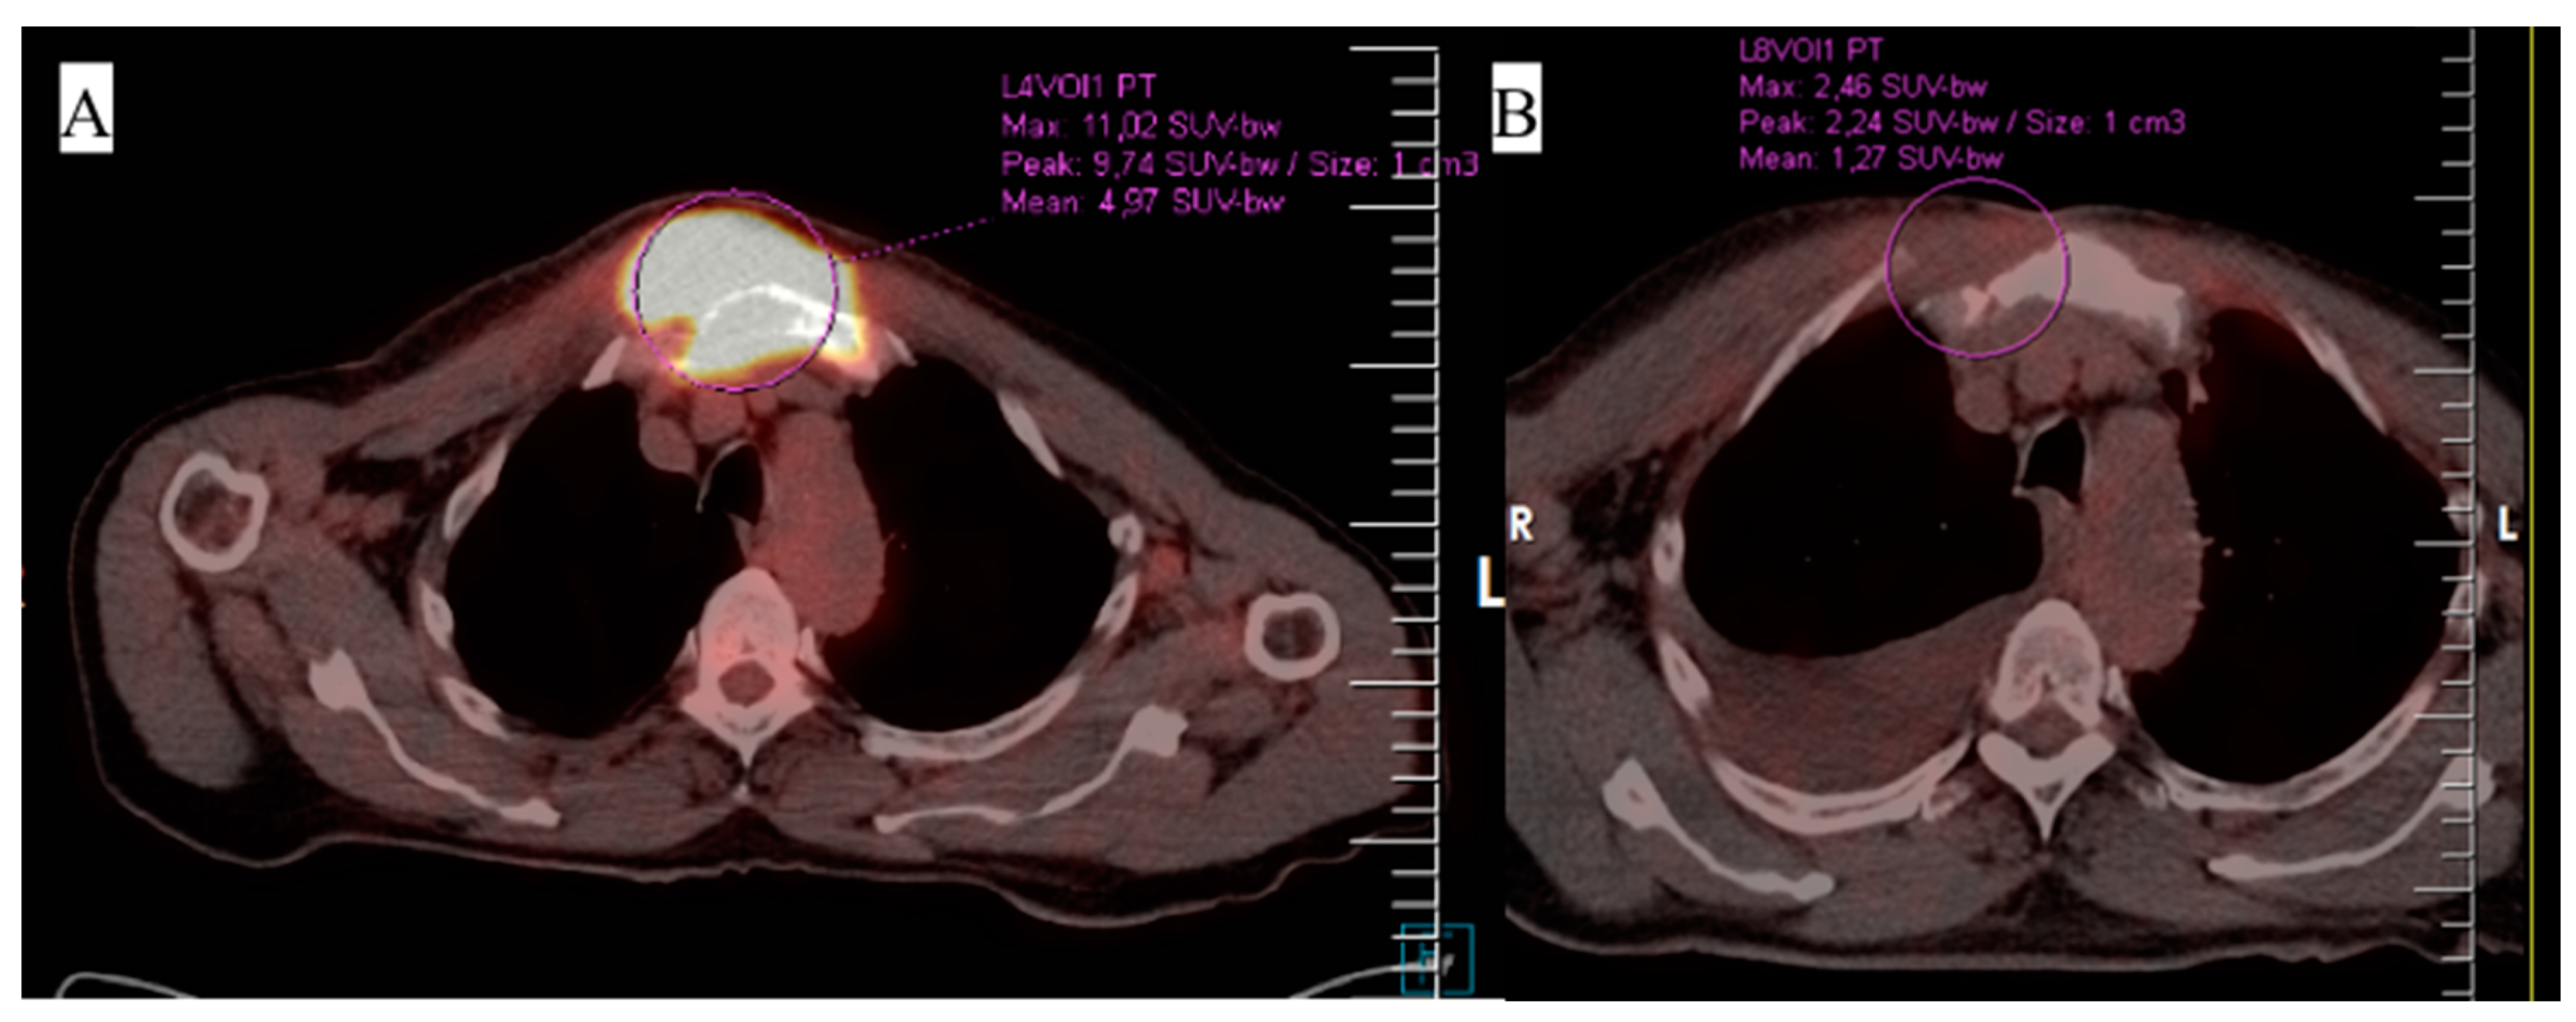

3. Case 1

4. Case 2